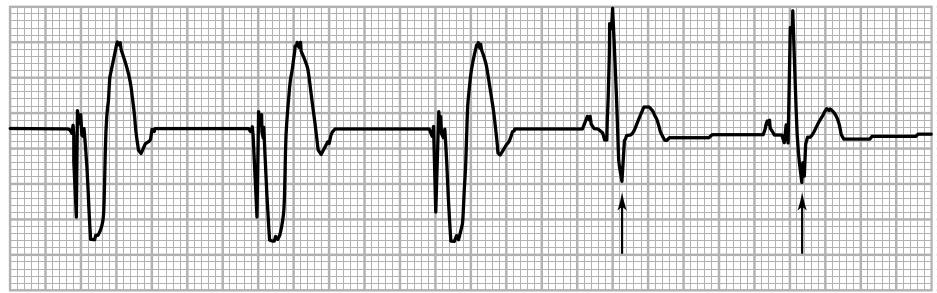

Pacemaker implanted 2 weeks back, recurrent syncope

v_non_capture.jpg